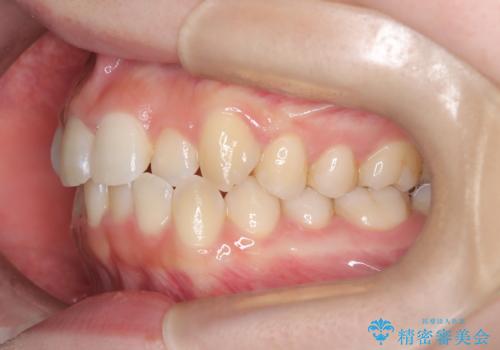

- 右上の前歯(2番)が下の歯より内側に入っている反対咬合を主訴にご来院されました。精密な検査の結果、この反対咬合を解消するためには、右上の歯列に前歯を出すためのスペースを確保する必要があると判明しました。患者様のご希望に合わせ、透明で目立たないインビザライン(マウスピース矯正)による治療計画を立案。奥歯全体を奥へ動かす遠心移動でスペースを作り、反対咬合を解消することを目指します。

今回の矯正治療では、透明なマウスピース型の装置インビザラインを使用しました。治療は、緻密なデジタル計画に基づき、奥歯から順に歯列全体を後方へ移動させる遠心移動を実施し、前歯を前に出すためのスペースを確保しました。このスペースを利用して、内側に入り込んでいた右上2番をスムーズに前方に誘導し、正常な咬み合わせへと改善。目立たないインビザラインで、機能的な咬み合わせと美しい前歯の並びを獲得していただけました。